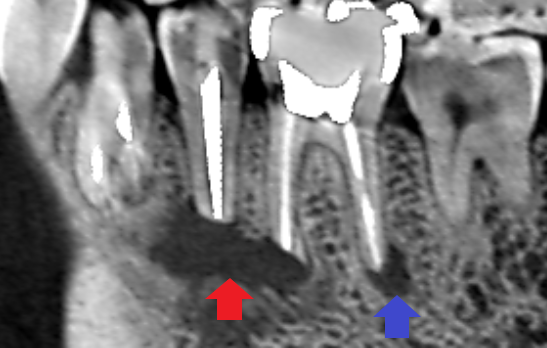

精密根管治療1年後の経過観察時の矢状断のCT画像です。赤い矢印先にあった下顎第二小臼歯と下顎第一大臼歯の近心根の両方の根にまたがるほど大きかった膿の影は消え、歯槽骨が再生しています。また、青い矢印の先にあった下顎第一大臼歯の遠心根の膿の影も消え歯槽骨が再生しています。

本ケースは、精密再根管治療のみで膿が改善しました。外科的歯内療法で治らなかった理由はやはり根管の感染除去が十分でなかったことだと思われます。逆に、精密根管治療をしていれば外科手術に至らなかった可能性も高いです。